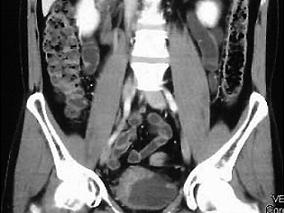

1小时条评论患者男性,深圳人,46岁。 主诉:间歇性无痛性肉眼血尿5个月。 现病史:患者5个月前无明显诱因出现间歇性无痛性肉眼血尿,褐红色,偶伴小血块,无腰痛、发热,无尿少、排尿中断,无尿频、尿急、尿痛,无夜尿增多、排尿困难等,于外院就诊,确诊膀胱癌,单发,位于...